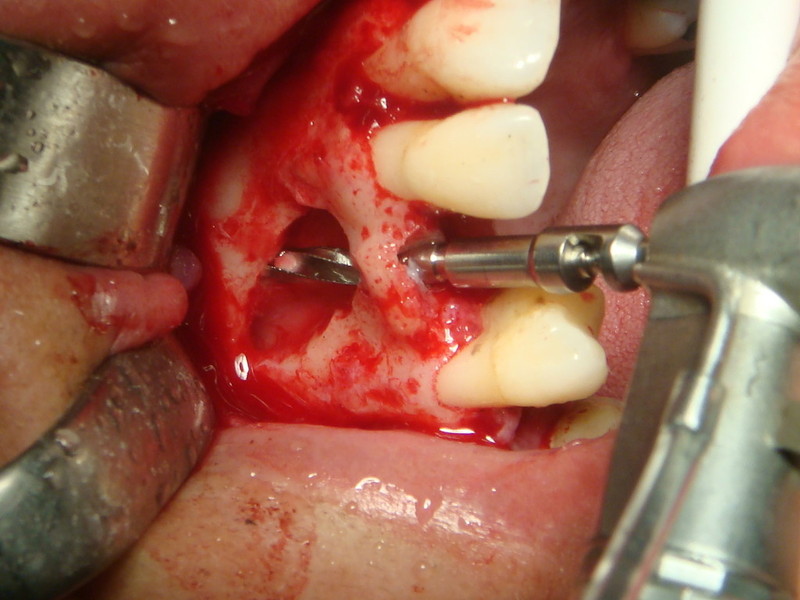

Estrazione di un canino incluso e contestuale inserimenti di impianto e innesto osso eterologo